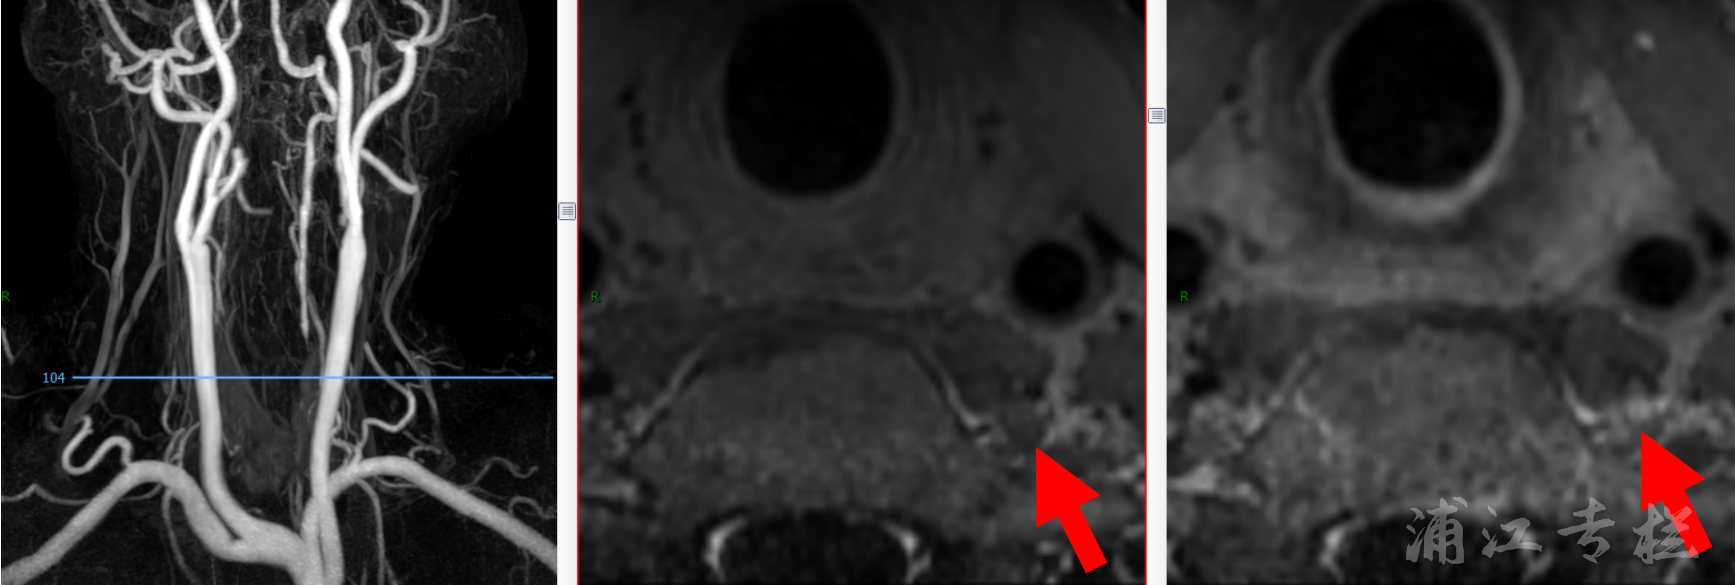

术前HR-MR 血管壁评估:

MRA提示双侧椎动脉V1段闭塞,V2-V4段血管可见显影,左侧椎动脉较粗,考虑为相对优势侧。

箭头示椎动脉V1段闭塞处官腔内的斑块。

Snap序列高信号提示管腔斑块是血栓成分为主。

高分辨MR连续层面提示左侧椎动脉闭塞远端官腔可见。

高分辨MR提示左侧椎动脉闭塞处增强前成等信号,增强后成高信号。